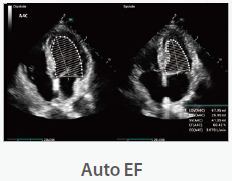

Mindray Ultrasound Consona N9